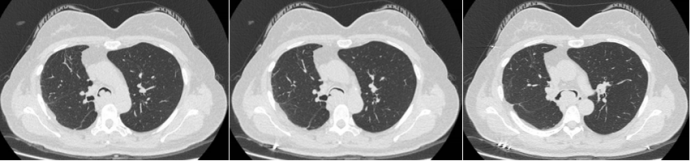

病例1:65岁男性患者,因“发热伴咳嗽、咳痰、气促5天,加重10小时”入院。诊断为危重症人感染H7N9禽流感并发重症肺炎、重度ARDS、急性肾衰竭及多器官功能障碍综合征,同时合并2型糖尿病及高血压3级。在呼吸机高度参数支持下行FBPDT,快速建立气道通路,为后续治疗赢得时间,患者经积极治疗后康复。患者入院胸部CT见图1,治疗前后胸片对比见图2。

图片

1  患者胸部CT